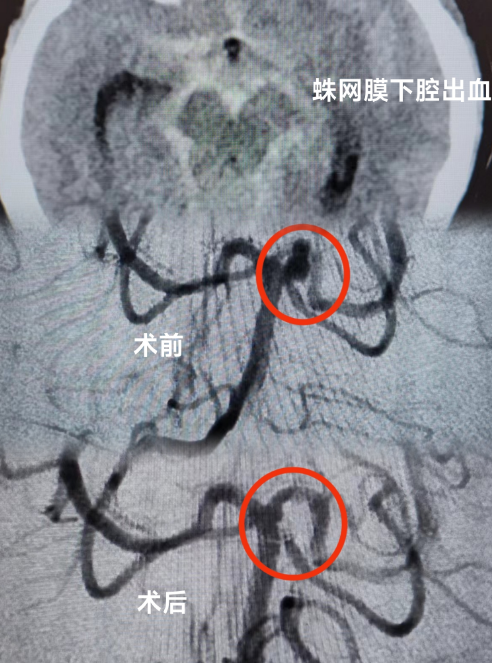

当天,患者被送到急诊科时,医生为她紧急安排头颅CT检查,发现患者有蛛网膜下腔出血的情况。蛛网膜下腔出血通常病情比较严重,可诱发脑血管痉挛,进而继发出现脑梗死,危害患者生命。为了帮助患者尽快脱离危险,急诊科立即联系了神经外科、重症医学科及心血管内科当班医生进行联合会诊。

捆绑调教 多学科专家团队结合患者检查结果,认真分析患者病情,判断患者动脉瘤破裂出血可能性大,同时合并有急性冠脉综合征,不排除急性心梗的可能。考虑到患者病情的危重性及复杂性,专家团队建议患者入住重症监护病房(ICU),紧接着由神经外科医师团队运用神经介入技术为患者进行脑血管疾病诊治,同时神经外科医师与心血管内科介入医师通力合作,排查了心脏冠脉相关疾病。期间,麻醉科、重症医学科医师团队也全程为患者保驾护航,排查手术各种风险。

手术历经约3个小时,专家团队排除万难,为患者完成了全脑血管、冠脉造影术,以及颅内动脉瘤介入栓塞术手术,术后患者恢复良好。